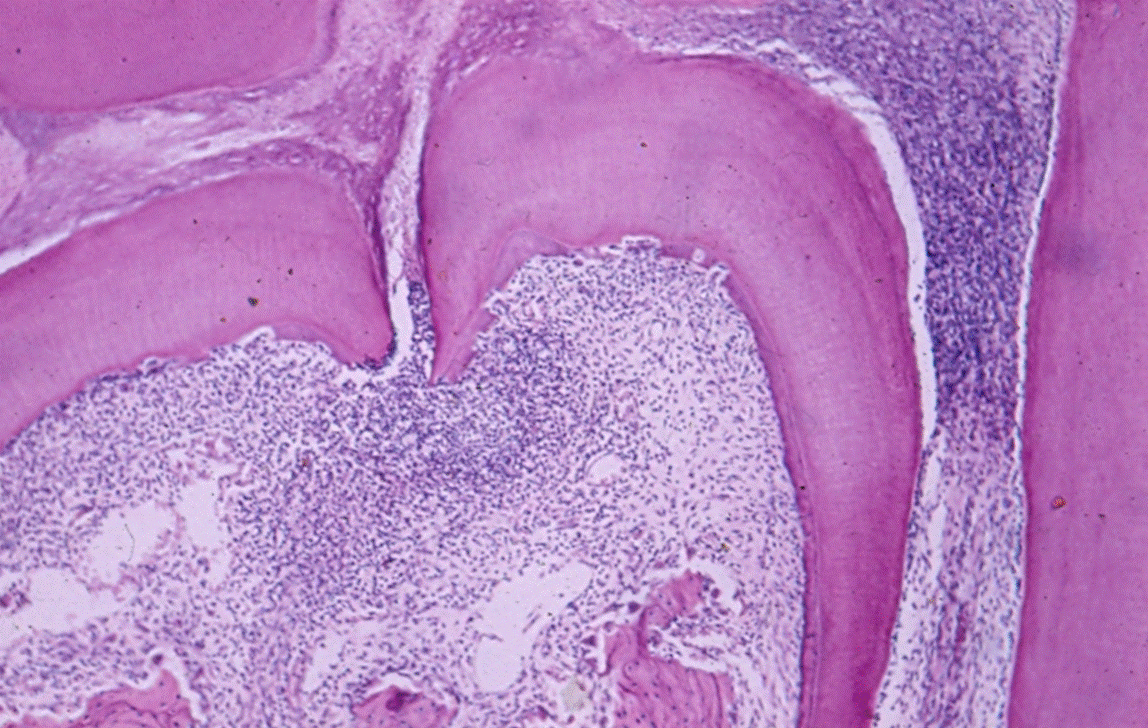

Figure 1. Infection in furcation. H&E histologic image showing infiltration in the furcation area

Lateral canals: Tagger, et al. showed that when the pulp becomes necrotic in monkeys’, dogs’ and rats’ teeth an inflammatory response occurs in the periodontal ligament, apical foramen or in the furcation areas in 21% of the teeth that were examined (Figure 1) [3,11]. In human specimens, under a microscope, canals were found in the furcation area in 74% of the teeth [12]. Using Basic Fuchsin stain accessory canals were shown in 57% and with the fluid filtration method, in 1% [13,14]. The variability in the number of canals in human teeth is probably dependent on the material (origin of the teeth) and the methods used for detection of the canals [15]. Accessory canals could be found anywhere along the root, mostly in the apical third (Figure 2) [16]. Seltzer et al. reported that pulpal inflammation may cause an inflammatory reaction in the interradicular periodontal tissues [17]. Histologically, inflammatory response can be present in front of the openings of accessory canals, but its clinical impact is negligible [18-20] (Figure 3). However, it should be noted that when a lesion exists in the furcation area, both treatment and prognosis change according to the presence of accessory canals [21]. Lin et al 2008 suggest that teeth with furcation involvement should be treated with bonding after the root canal treatment [22].